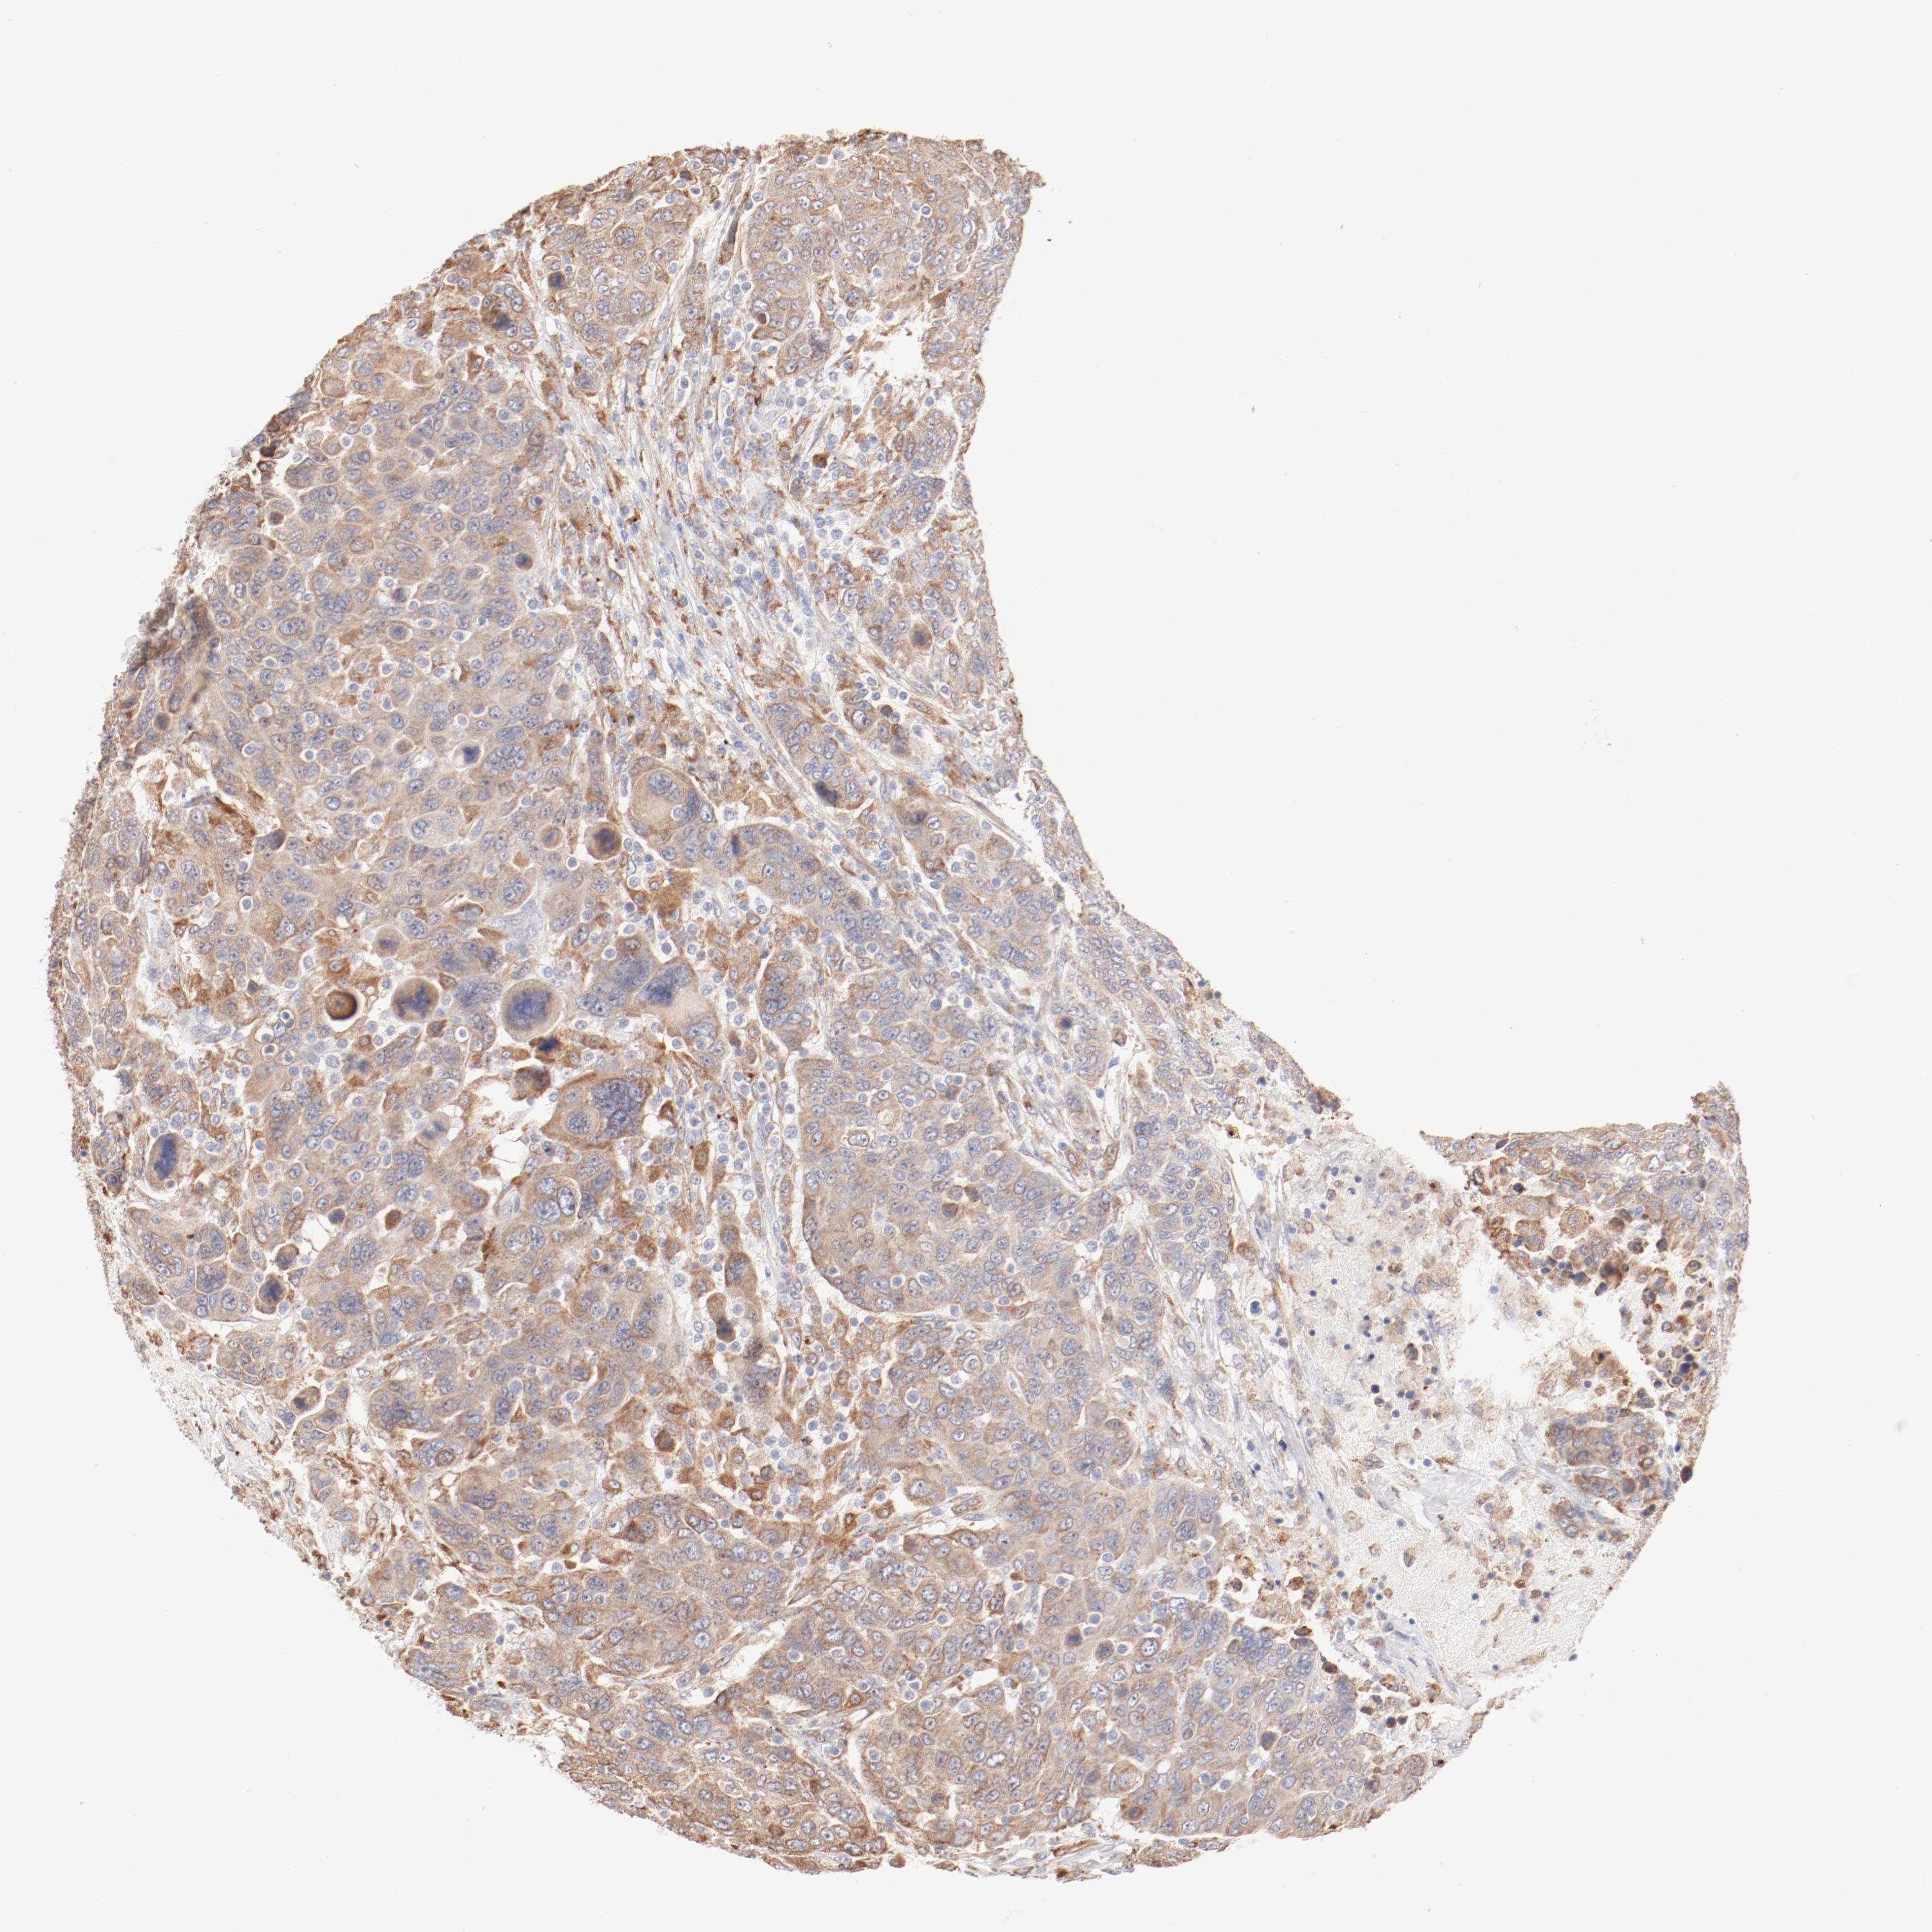

BRCA TCGA BRCA VALIDATION PROTEIN EXPRESSION

ANTIBODIES

AND

VALIDATION